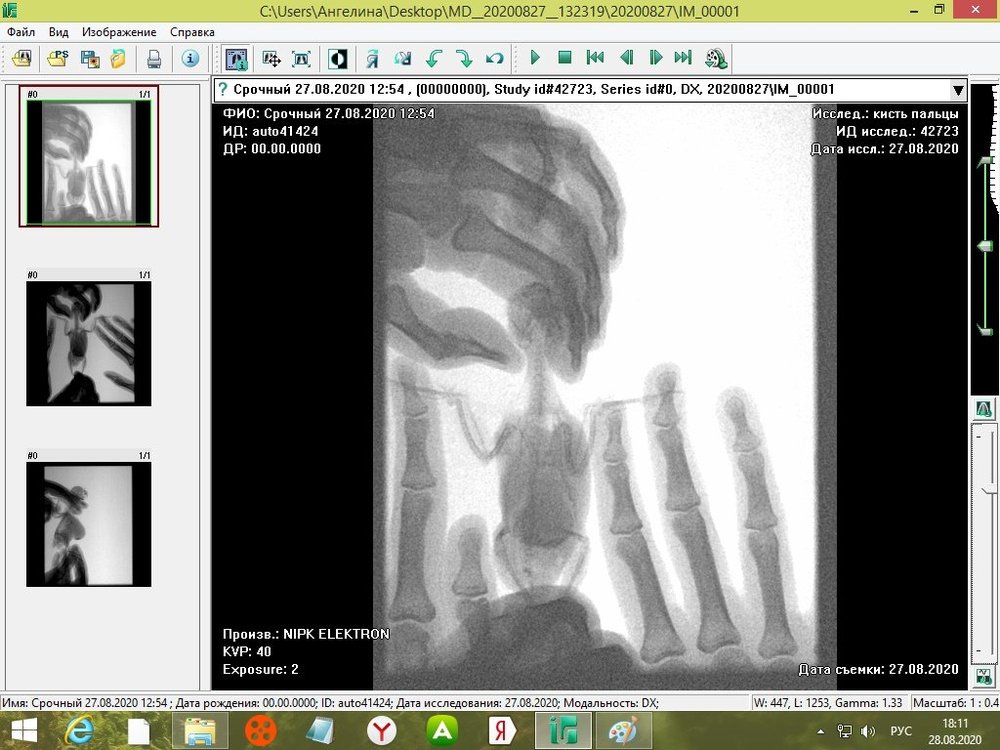

tanushka-sol2020 Опубликовано 27 августа, 2020 Автор #15 Опубликовано 27 августа, 2020 Некадрированные исходные снимки --- щёлкните полосу ниже. Скрытый текст

Кузяныч Опубликовано 28 августа, 2020 #16 Опубликовано 28 августа, 2020 Ох, бедная волнушка... В помёте на шли бактерии (++), слизь (+), жир (+), клетчатку (++)... Есть и непонятные для меня записи... По рентгену на втором снимке справа мне видится что эта огромная припухлость --- растянутый зоб... 18.08.2020 в 17:16, tanushka-sol2020 сказал: Что за опухоль? Она в моих руках меняется: то сморщится, то раздувается как шар надувной... Неужели, действительно зоб?... @tanushka-sol2020, срочно звоните Зосе, просите посмотреть снимки. Мазок из клюва... уф-ф... не знаю пока на сколько он нужен... Если на нистатине птице легче, то давайте его --- придерживайтесь дозировок, что давала вам Зося. Расположите лесенку горизонтально чтоб попугайчик экономил силы. Установите всё как можно ниже к полу. Проверьте, чтоб птичка не пыталась лезть выше и не висла на стенке. Помёт оранжевый... возможно, действительно, печень страдает... Карсил не отменяйте... За гепатовет и как вообще быть я не могу сказать. Нужно чтоб Зося посмотрела рентген. Свяжитесь, пожалуйста, с ней. У меня такое впечатление, что у этой волнушки растянут зоб и от этого плохо уходит и застаивается, протухая, пища.

tanushka-sol2020 Опубликовано 28 августа, 2020 Автор #17 Опубликовано 28 августа, 2020 (изменено) @Кузяныч К сожалению, от нистатина у нее сильно страдает печень. Я не стала ей давать, почти 3 недели принимали. Но срыгивание снова вернулось. Когда я собирала мазок из глотки, она потом срыгнула на одежду. Капли были песочного цвета и консистенция, как каша жиденькая. Но с запахом. Переживаю, вдруг неправильно сделала мазок, впервые же. Во вторнике будет готов анализ. Отпишусь. Рентген делали в больнице, я их кое-как уговорила. Первый "блин с комом", тоже выложила. Вдруг качества нет на снимке, что показал. Завтра Зосе позвоню. Спасибо, что ответили. Эти снимки неудачные выше, племянница скидывала. Я немного контраст отрегулировала, чтобы было видно. Изменено 28 августа, 2020 пользователем tanushka-sol2020